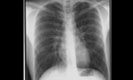

75 jähriger Patient Zunehmende Belastungsdyspnoe. Ihre Diagnose? Nebenbefunde?

Röntgenfall des Monats Januar 2018 mit Auflösung

17 jähriger Patient Sturz auf den Rücken beim Crossbiken. Schmerzen HWS und Thorax. Fraktur, Pneumothorax, andere Pathologien? Weitere bildgebende Diagnostik? Welche? Warum?

48 jähriger Patient. Klinische Angaben: Thoraxschmerzen, afebril, hypertensiv entgleist. Fragestellung: Infektzeichen? Kardiale Kompensation? Diagnose? Weitere radiologische Diagnostik?

78 jähriger Patient mit zunehmender Dyspnoe und Thoraxschmerzen

74 jährige Patientin mit diffusen Skelettschmerzen und akut aufgetretener Dyspnoe. Z.n. Mammakarzinom rechts.